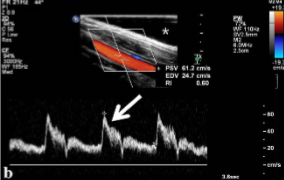

In the sagittal plane and with duplex/color flow imaging, what should the doppler angle be set at for accurate PSVs?

Less than or equal to 60 degrees

What doppler angle is the standard/best for duplex imaging?

@ 60 degrees

What doppler angle should be used for duplex imaging?